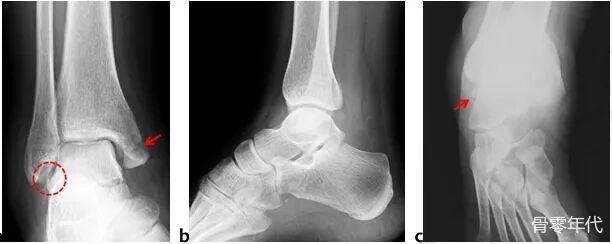

一名34岁的女性在踝关节内翻扭伤后立即入住我们的急诊科。就诊时,她无法负重,脚踝严重肿胀。主动和被动踝关节运动疼痛且受限。内踝和外踝均有压痛。神经血管检查结果正常。踝关节的直接放射学检查显示移位的内踝骨折和腓骨尖端的骨碎片(图1a,1b)。此外,斜X光片更清楚地描绘了碎片。为了了解损伤模式,进行了进一步的计算机断层扫描(CT)检查。CT显示该片段在 ATFL附着时从距骨撕脱(图 2a、2b、2c)。由于患者有移位的内踝骨折和踝关节不稳定,因此计划手术固定骨折。

内踝骨折和腓骨尖端的骨碎片